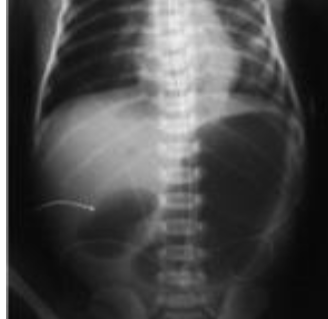

- Anterio-posterior [AP] chest radiograph shows multiple cystic lesions inâ (1 -the middle and lower zones of the left hemi-thorax with ill-defined left hemi diaphragm. There is mediastinal shift toward the right. These lesions are -bowel loops inside the left hemi-thorax. The film is over exposed (over .(penetration

- The diagnosis is Left Sided Congenital Diaphragmatic Hernia (CDH). This - (2 is called bockdalic CDH. CDH is usually in the left side (90 %). The defect is found in the posterio-lateral aspect of the diaphragm. CDH is associated with .lungs hypoplasia in the same side and to a lesser extent in the opposite side .This may be complicated by pulmonary hypertension and severe hypoxemia

- The treatment of CDH is immediate endo-tracheal incubation if it is - (3 diagnosed in-utero or if it is highly suspected after birth (with following symptoms and; respiratory distress (RD), cyanosis, asymmetrical chest movement, bowel sounds heard in the chest and scaphoid abdomen). After intubation, the patients is put on mechanical ventilator and the pulmonary hypertension [PH] is controlled and hypoxemia is reversed. PH and severe hypoxemia may require inhaled Nitric Oxide [iNO], High frequency Oscillatory Ventilation [HFOV] and Exogenous Surfactant administration through endotracheal tube [ETT]. After the stabilization of the arterial blood gases the patient is taken to suture the defect. If the defect is large, a mesh,[ABGs] device may be used. The most important differential diagnosis is Cystic .Adenomatoid Malformation [CAM]